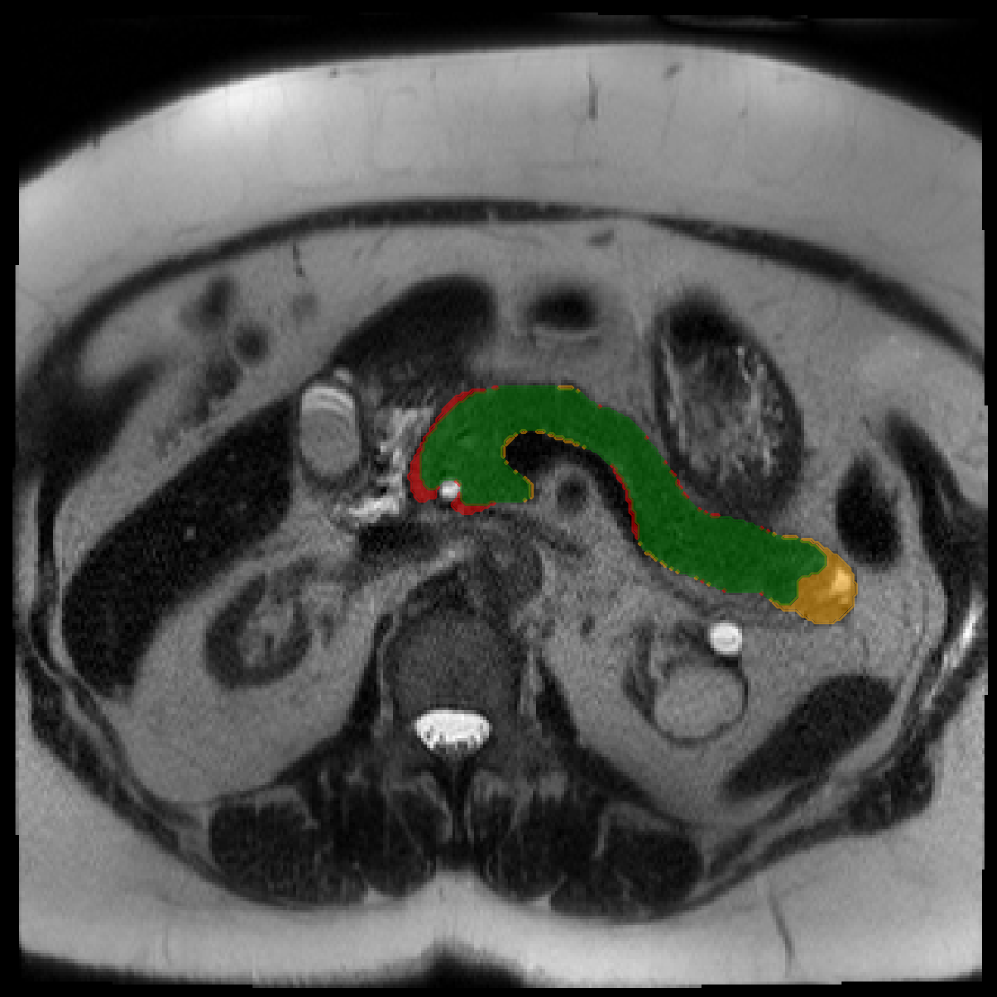

Accurate pancreas segmentation is a critical prerequisite for precise cyst analysis and classification. Recently, we developed PanSegNet [zhang2025large], a novel segmentation architecture incorporating linear self-attention layers [zhang2022dynamic] within the nnUNet framework [isensee2021nnu] to enhance global information modeling capabilities while maintaining computational efficiency (Fig. 1). PanSegNet demonstrated exceptional segmentation performance across both T1W and T2W modalities, achieving mean dice scores of 86.817.30% and 89.626.38%, respectively (Table 1, Fig. 2b-c). This performance significantly exceeded that of Swin-UNETR [hatamizadeh2021swin], one of the most used state-of-the-art transformer-based medical segmentation models, which achieved dice scores of 79.091.40% and 76.290.66% for T1W and T2W, respectively (). In this study, we integrated PanSegNet into our Cyst-X engine along with a classifier for risk prediction. In Section 2.2, we show that the choice of segmentation model affects the classification results. The performance advantage of PanSegNet was consistent across all seven medical centers, demonstrating robust generalization despite variations in imaging protocols and equipment (Table 1). This cross-institutional reliability is particularly important for clinical applications, where model performance must remain consistent regardless of imaging site or acquisition parameters.

2.2.1 Importance of accurate pancreas segmentation in classification

To assess the importance of accurate pancreas segmentation in classification, we evaluated how different ROI sources affect DenseNet-121’s performance. Specifically, we compared classification results using ROIs generated by PanSegNet and Swin-UNETR, both under centralized learning, against a baseline using radiologist-defined ROIs. As shown in Table 2, using PanSegNet’s masks resulted in only a modest performance decline, reflecting its strong segmentation quality. In contrast, Swin-UNETR led to a more substantial drop, demonstrating that inferior segmentation can directly compromise classification. For 3-class classification, the mean AUC dropped from 75.59% (radiologist ROI) to 72.26% with PanSegNet, and further to 66.95% with Swin-UNETR on T1-weighted images. On T2-weighted scans, the AUC declined from 81.09% to 74.18% (PanSegNet) and to 69.63% (Swin-UNETR). A similar trend was observed in 2-class classification: on T1W, AUC dropped from 78.13% to 74.84% (PanSegNet) and 70.20% (Swin-UNETR); on T2W, from 82.37% to 77.01% and 68.92%, respectively. These results emphasize that accurate segmentation—particularly via PanSegNet—is not only essential for volume estimation but also critical to preserving downstream classification performance in the Cyst-X pipeline.

Each patient was categorized into one of these three ground truth classes: no risk/control, IPMN low-risk, or IPMN high-risk. To evaluate variability in image acquisition, we applied uniform manifold approximation and projection (UMAP) to image quality indicators, revealing distinct clustering patterns by imaging center and slice thickness. This heterogeneity reflects real-world clinical variability, enhancing the dataset’s generalizability while presenting technical challenges for model development. Fig. 6 shows examples of low-grade, high-grade, and cancer developing IPMNs from the Cyst-X dataset.